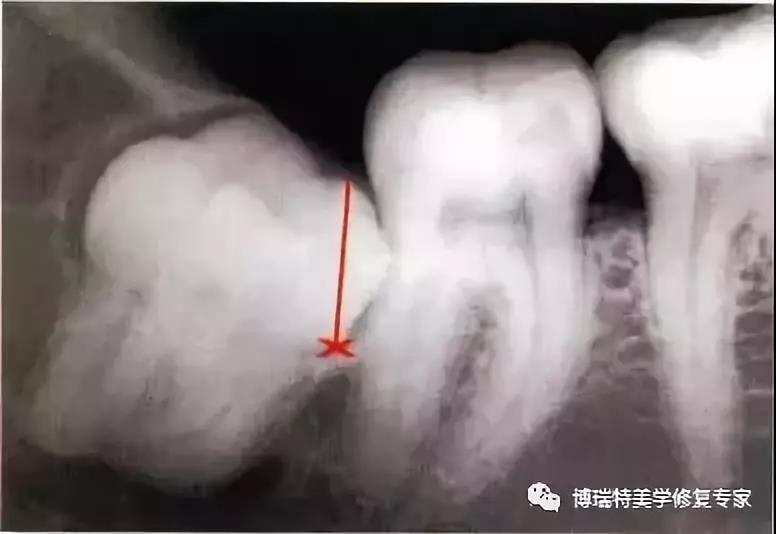

1、下颌第三磨牙阻生。代表牙槽窝深度的红线表明从牙槽嵴顶到釉牙骨质界间在近中颊角方向上的距离。考虑到患者的年龄,阻生牙牙槽窝的近中骨壁较容易以第二磨牙牙根旁的硬骨板为基础分化再生。因此,该患者第二磨牙牙槽骨修复重建的预后较好。